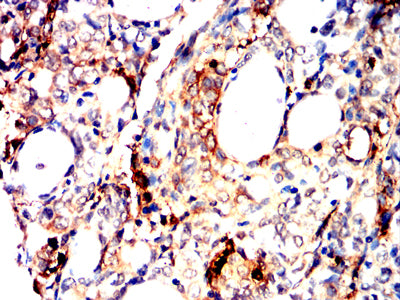

Immunohistochemical analysis of paraffin-embedded rat kidney tissues using TPSAB1 mouse mAb with DAB staining.

Immunohistochemical analysis of paraffin-embedded human lung cancer tissues using TPSAB1 mouse mAb with DAB staining.

Immunohistochemical analysis of paraffin-embedded human cervical cancer tissues using TPSAB1 mouse mAb with DAB staining.